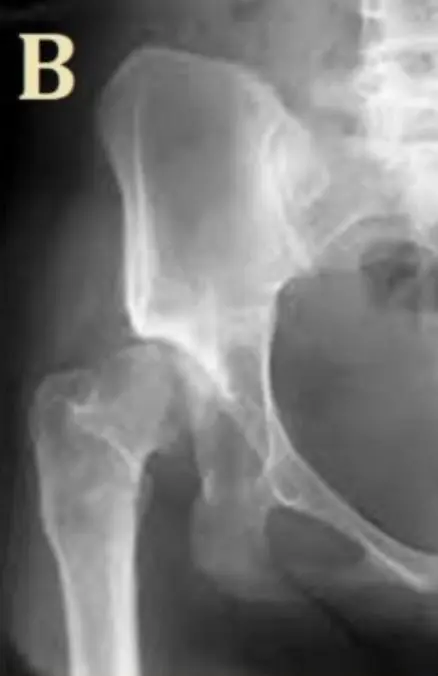

Posterior Hip Dislocation

- Diagnosis: Posterior Hip Dislocation.

- Limb Position: The affected limb is shortened, adducted, and internally rotated.

- Radiological Sign: The femoral head is seen above the acetabulum.

- Management: Emergency reduction under sedation/anesthesia by orthopedics.